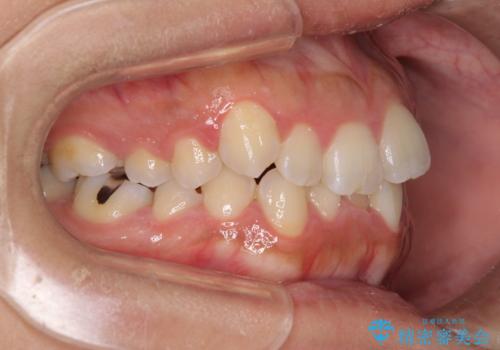

デコボコを解消する過程で、歯列の拡大により口元が突出する可能性があったため、4本の親知らずを抜歯しておき、歯列全体が後方に移動するように設計し、インビザラインにて矯正治療を行うこととしました。

日々の装着時間をしっかりと守って治療の臨んでくださったため、治療前のシミュレーションに近い形で矯正治療を進めて行くことができました。